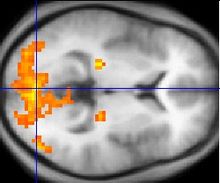

L'éveil au repos qui est expérimenté au cours de la technique de MT crée plus de connectivité dans les régions frontales du cerveau, les zones qui contrôlent les actions impulsives, le jugement, et les compétences sociales. Cela signifie que les différentes parties du cerveau travaillent davantage en concorde. Ce fonctionnement intégré, à son tour, renforce les circuits, la création d'une meilleure communication d'une partie du cerveau avec une autre, il devient donc plus "cohérent".